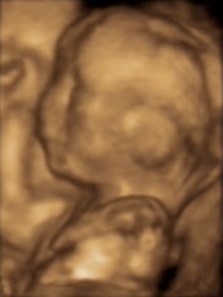

Photos: New state laws ban abortions even for serious deformities that would result in a chlid doomed to pain, suffering, or death. Shown: Microcephalic fetus with brain deformity, conjoined twins, infant with two faces.